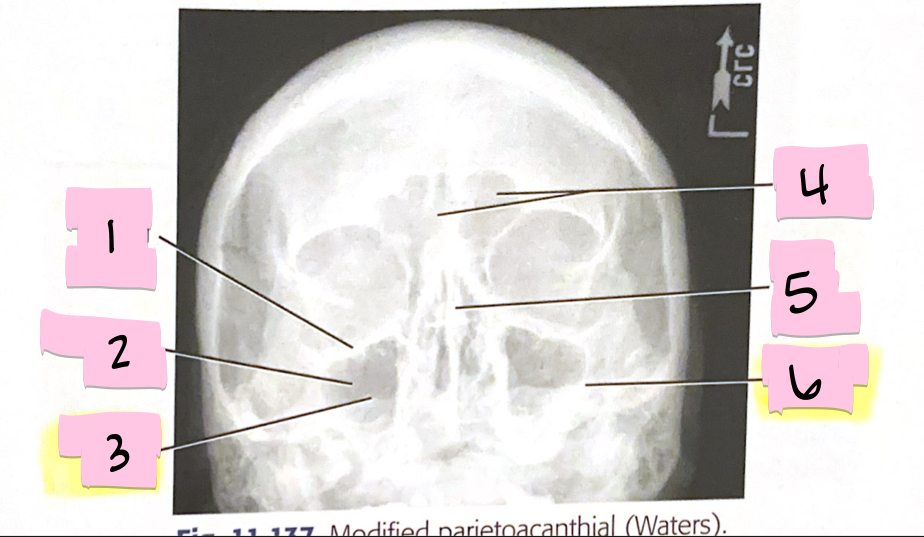

What is 1 pointing to?

Inferior orbital margin

What is 2 pointing to?

Maxillary sinus

What is 3 pointing to?

Petrous ridge

What is 4 pointing to?

Frontal sinuses

What is 5 pointing to?

Bony nasal septum

What is 6 pointing to?

Petrous ridge